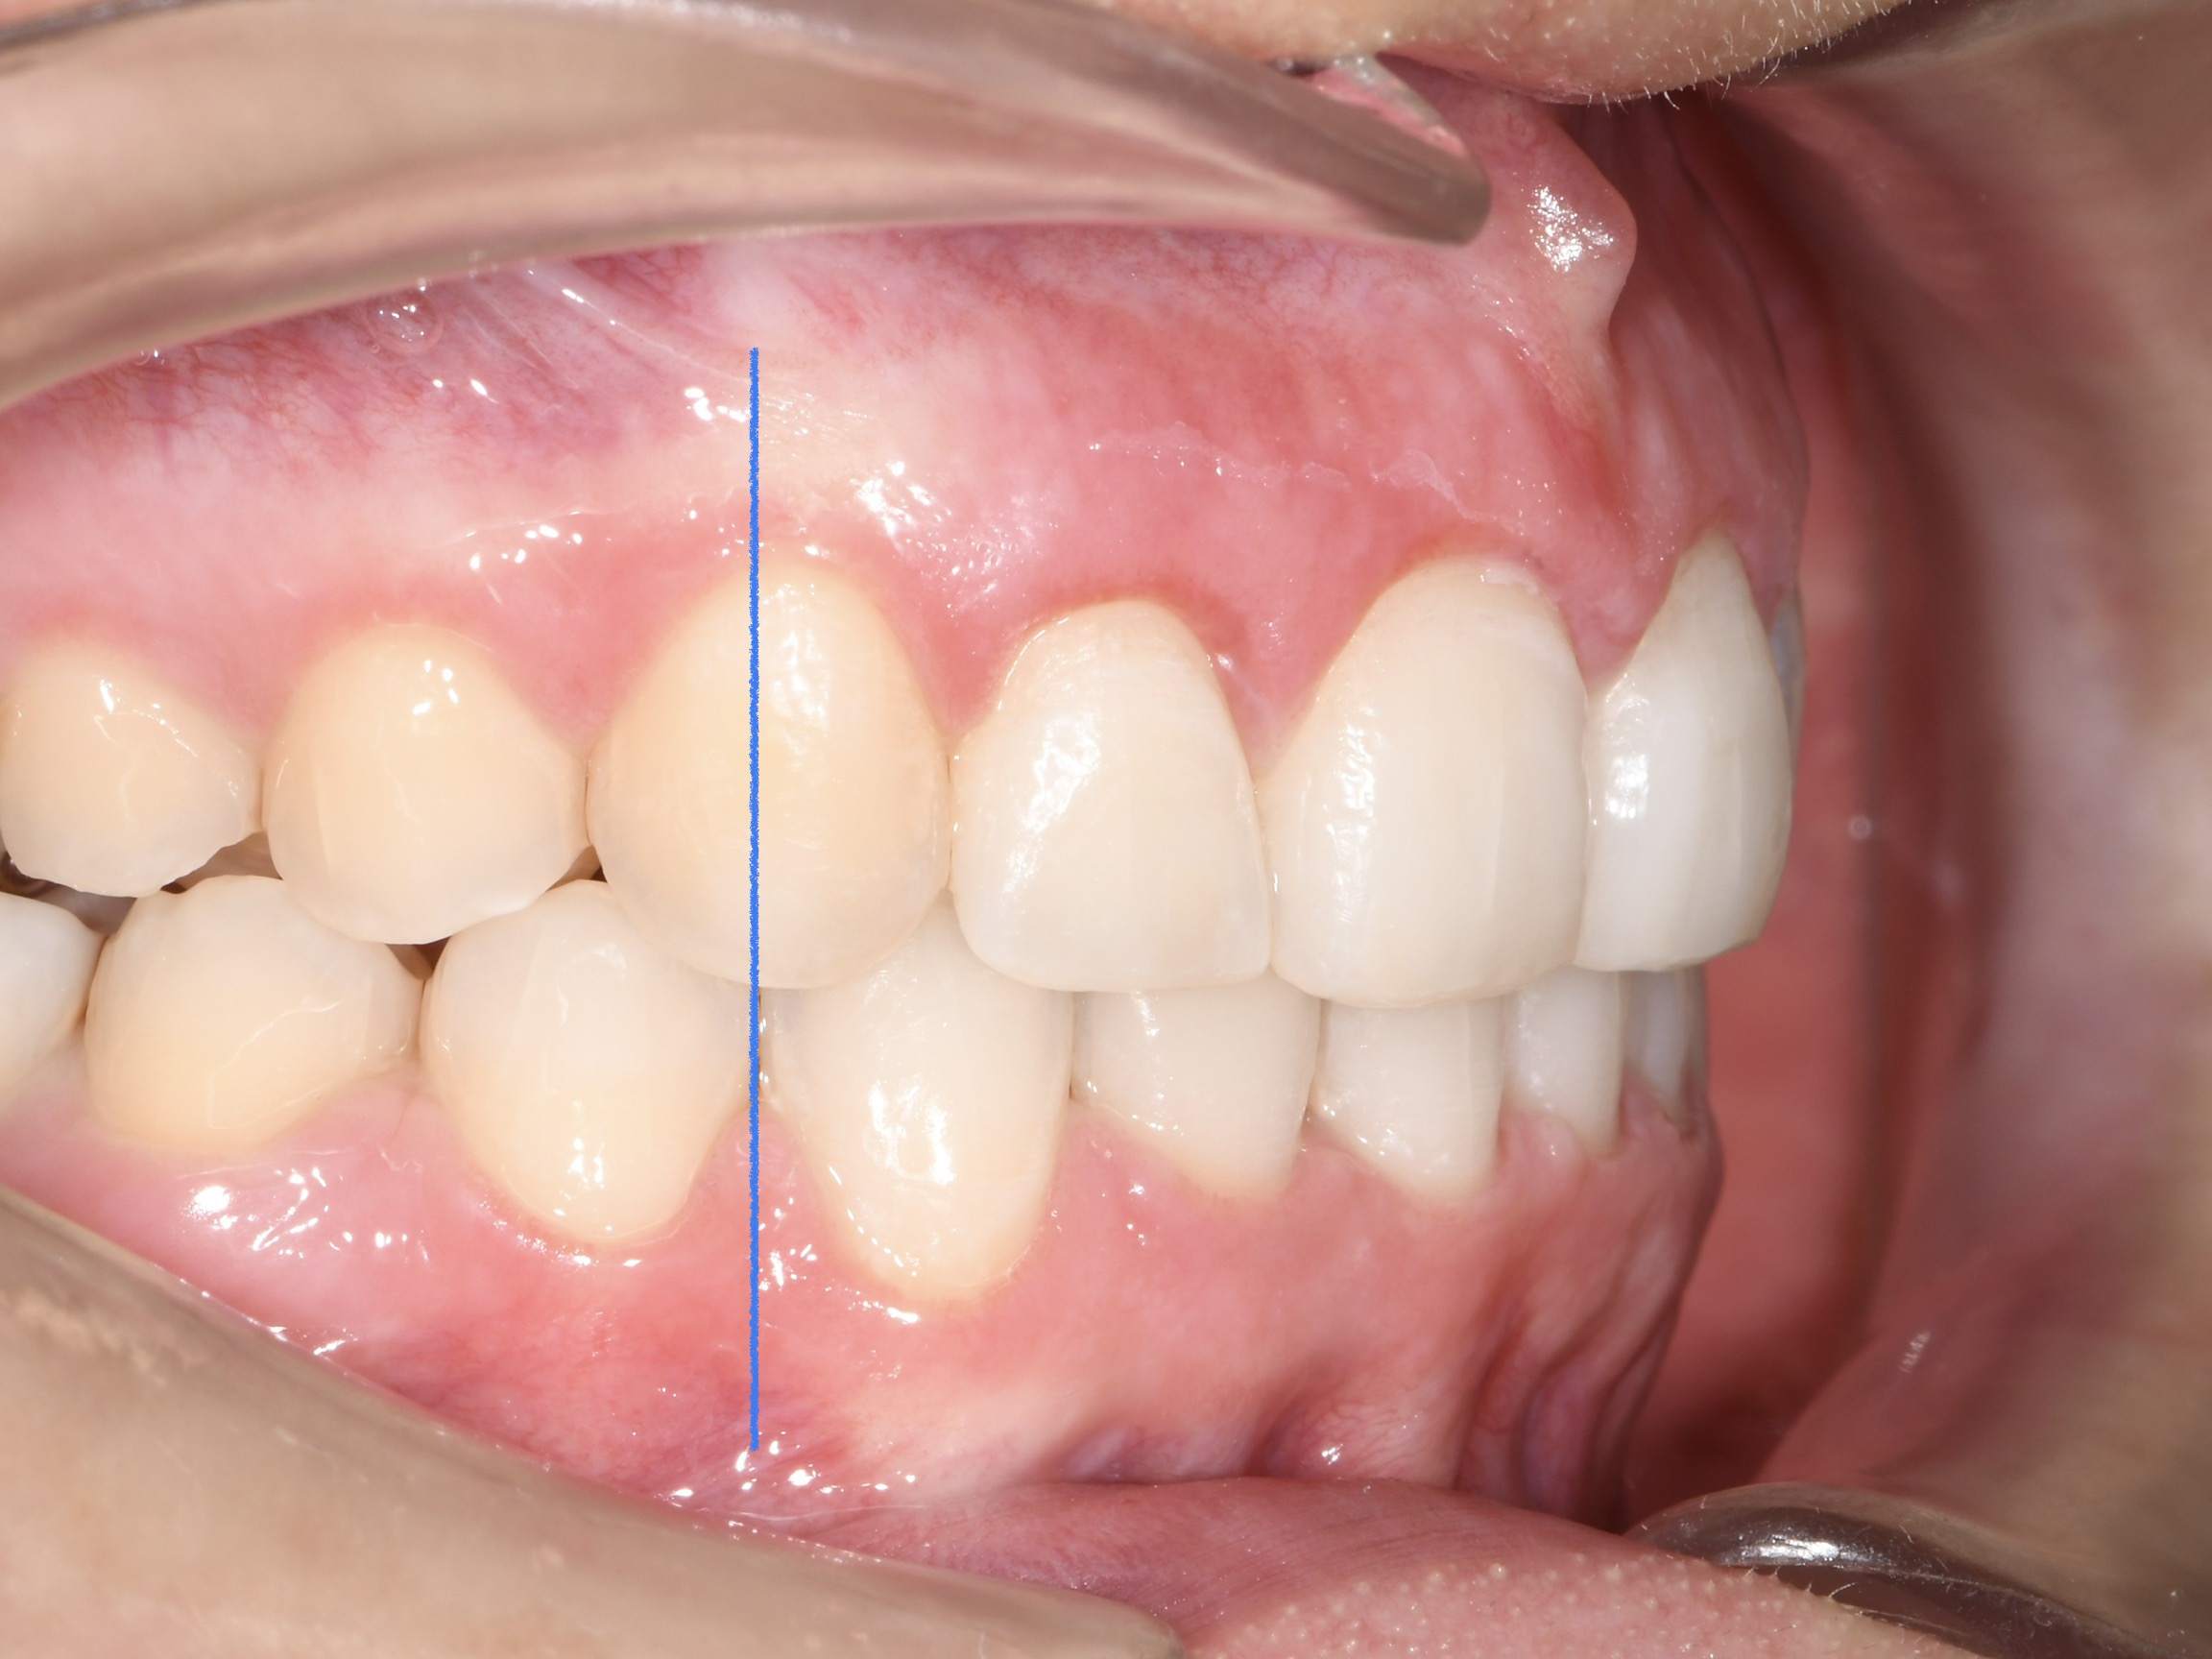

Az elmúlt évekből rengeteg szakmai referenciát tudnánk bemutatni, amelyek különböző fogszabályozási problémákat oldottak meg. Válogatva a több száz esetből, ezen az oldalon olyan képeket, információkat igyekeztünk bemutatni, amelyeknek a segítségével a jövőbeni pácienseinknek azt tudjuk üzenni: A Te fogsorod is lehet gyönyörű!